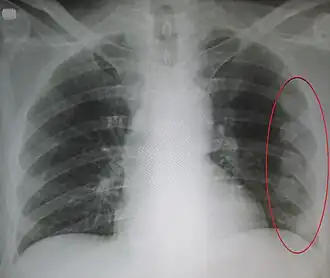

| Um raio-X mostrando múltiplas costelas quebradas do lado esquerdo da pessoa conforme marcado pela oval | |